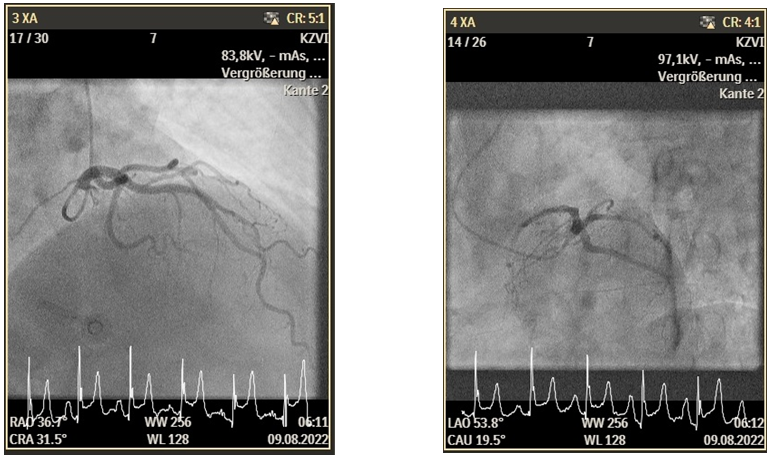

A 47-year-old female presented to our Emergency Department (ED) because of typical chest pain, the patient has never this pain, at admission day was the first time. This patient has no previous history of DM or hypertension. An electrocardiogram was performed, which showed sinus rhythm with ST elevation in II, III, and AVF. This Patient has a hs-TNI at 7ng/dl at hour 0 (normal 2.3-11.6 ng/l), 4 hours after the admission was hs-TNI at 600 ng/dl. The coronary angiogram was without a significant epicardial coronary artery disease. For further evaluation, we measured the microcirculatory resistance (IMR=15) and coronary flow reverse (CFR =3,7) which were not pathologic (Figure 1).

Figure 1. TEE Bilder.